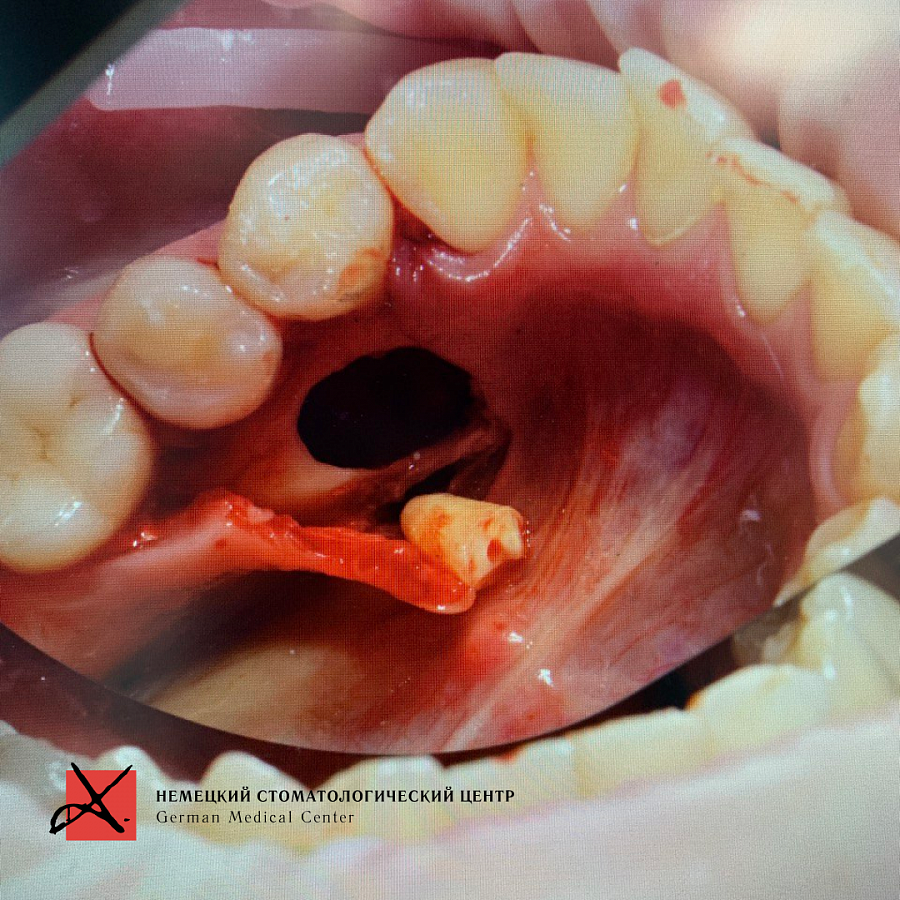

Пациент направлен врачом-ортодонтом с целью удаления ретинированных дистопированных зубов. У пациента аномалия: лишние зубы в передне-боковых отделах.

Зубы были удалены через окошко в кости, сделанное изнутри полости рта со стороны языка. Заживление прошло отлично, пациент ни на что не жалуется, соседние зубы не были повреждены.